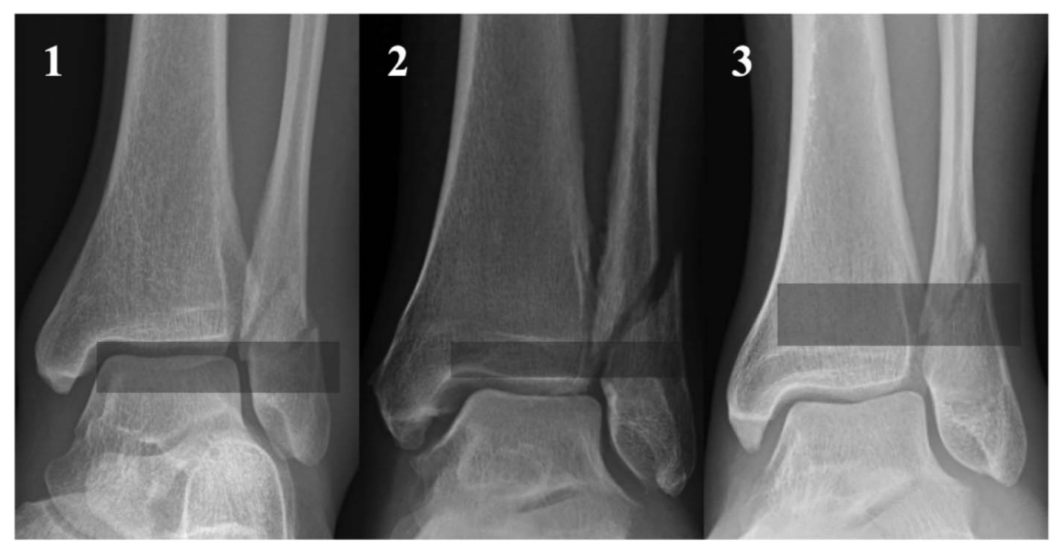

图2Danis-Weber B型骨折,根据近端骨折块最远端位置分区。1区定义为骨折块最远端位于胫骨远端关节面平面以下;2区为位于胫骨远端骺线闭合瘢痕与远端关节面之间;3区为骺线闭合瘢痕以上。

图3 分区示意图。

共有191例1区(止于胫骨远端关节平面下方)损伤,57处2区(止于胫骨远端骨骺线闭合瘢痕和胫骨远端关节面之间)损伤,39处3区(止于胫骨远端骨骺线闭合瘢痕以上)损伤。其中,17% (33名患者)的1区、42% (24名患者)的2区和74% (29名患者)的3区骨折合并下胫腓韧带损伤。

[Results: There were 191 zone 1 (ending below the plafond) injuries, 57 zone 2 (ending between the physeal scar and the plafond) injuries, and 39 zone 3 (ending above the physeal scar) injuries. Of these, 17% (33 patients) of zone 1, 42% (24) of zone 2, and 74% (29) of zone 3 fractures had syndesmotic injuries. The relative risk of syndesmotic injury of zone 1 compared with zone 2 was 2.4 (P , 0.001), zone 1 to zone 3 was 4.3 (P , 0.001), and zone 2 to zone 3 was 1.8 (P = 0.002). The interobserver and intraobserver reliability was excellent (k = 0.86, 0.94).]